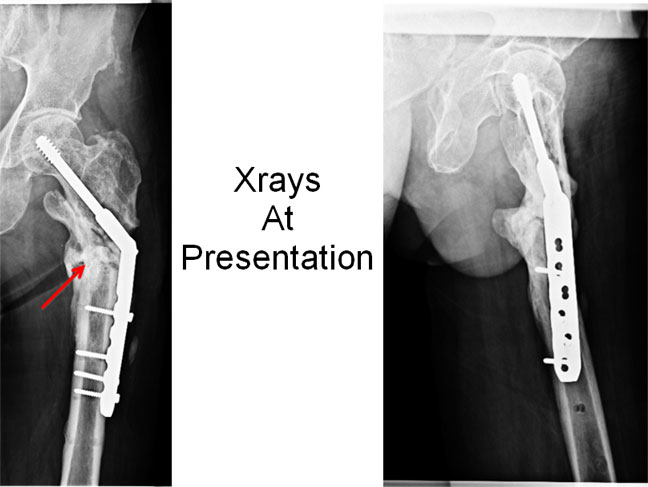

| Xrays At Presentation | ||

| The x-rays at presentation show loosening of screws, sclerosis at the fracture site, sequestrum (dead necrotic bone) (red arrow). | ||